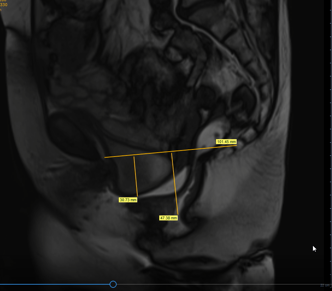

L’examen commence par des acquisitions en coupes standards pour avoir une vue d’ensemble des organes pelviens. S’ensuivent des images plus spécifiques, réalisées selon la pathologie recherchée, modulant les paramètres d’acquisition – pondération T1, T2, diffusion, etc. En cas d’injection de produit de contraste, de nouvelles séquences sont réalisées pour mettre en lumière les tissus anormaux.

Après l’examen, le radiologue analyse minutieusement les images obtenues à la recherche de signes pathologiques ou anomalies. Cette étape est cruciale pour aboutir à un diagnostic pelvien fiable. Le rapport d’IRM décrit les observations en termes d’anatomie, structure tissulaire, présence de masses, inflammations, ou modifications suspectes.

Le professionnel de santé doit maîtriser les nuances apportées par les différentes séquences pour distinguer, par exemple, un simple kyste bénin d’une tumeur ou détecter des signes précoces d’endométriose. Une corrélation avec l’historique médical du patient enrichit la lecture des images, ouvrant la voie à une orientation thérapeutique personnalisée.